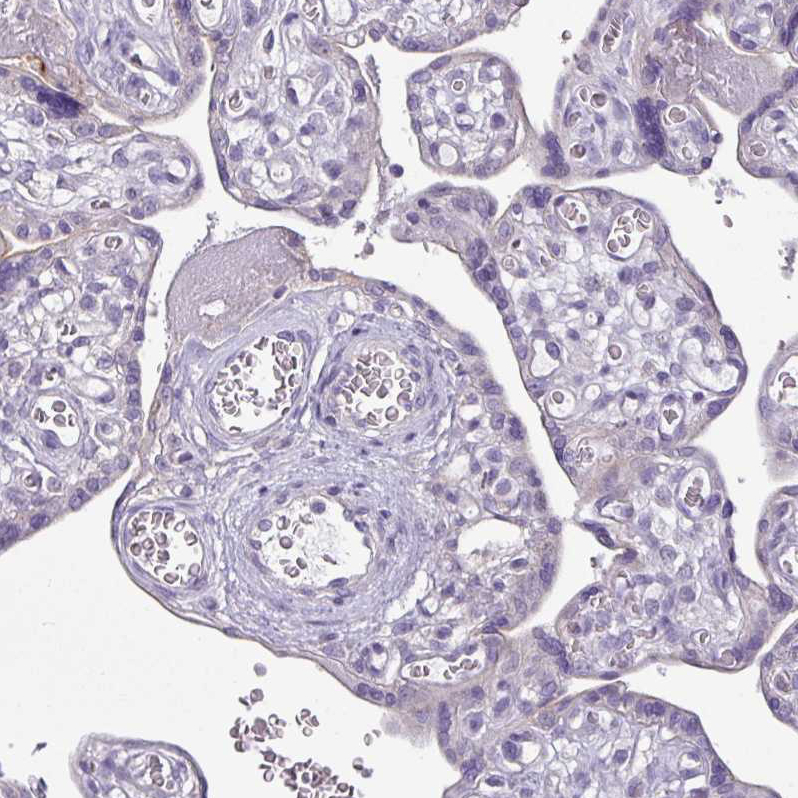

Immunohistochemical staining of human heart muscle shows moderate cytoplasmic positivity in cardiomyocytes.